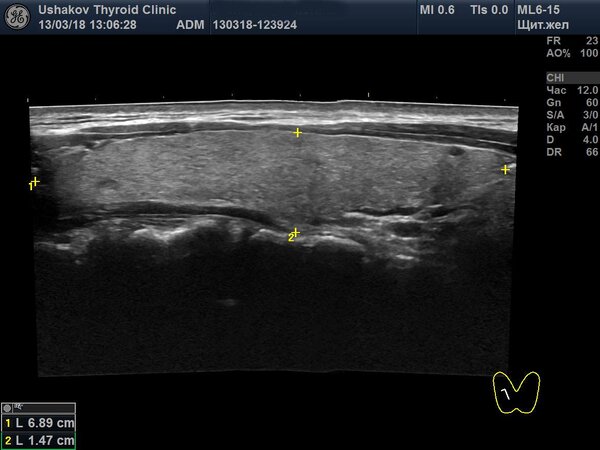

На этой неделе в нашей клинике был проведен осмотр пациентки, которая в 2001 году, в возрасте 13 лет, перенесла обширную операцию на щитовидной железе — так называемую 90% субтотальную субфасциальную резекцию. Это означает, что хирурги удалили почти всю ткань органа. Спустя 17 лет, во время ультразвукового исследования, мы с удивлением обнаружили, что все анатомические части щитовидной железы полностью восстановились, и визуальных признаков проведенной операции практически не осталось. Единственным напоминанием о хирургическом вмешательстве был тонкий, едва заметный рубец на коже.

Как же стало возможным такое полное восстановление? Во время операции хирург оставил примерно 10% ткани железы, преимущественно в тех областях, где проходят важные кровеносные сосуды и нервы. Пациентка в послеоперационный период не принимала заместительную гормональную терапию. Оставшаяся ткань, благодаря активной стимуляции со стороны нервной системы, запустила мощные процессы регенерации. В результате щитовидная железа не только восстановила свой первоначальный объем, но и полностью вернула свою анатомическую форму.